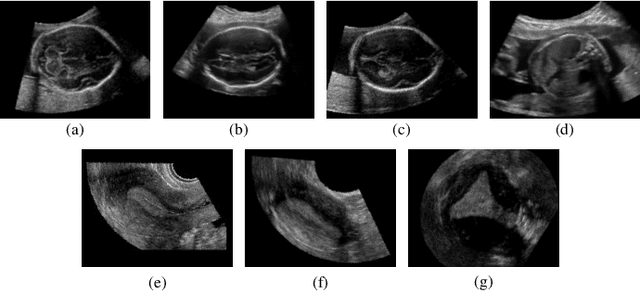

Abstract:Accurate standard plane (SP) localization is the fundamental step for prenatal ultrasound (US) diagnosis. Typically, dozens of US SPs are collected to determine the clinical diagnosis. 2D US has to perform scanning for each SP, which is time-consuming and operator-dependent. While 3D US containing multiple SPs in one shot has the inherent advantages of less user-dependency and more efficiency. Automatically locating SP in 3D US is very challenging due to the huge search space and large fetal posture variations. Our previous study proposed a deep reinforcement learning (RL) framework with an alignment module and active termination to localize SPs in 3D US automatically. However, termination of agent search in RL is important and affects the practical deployment. In this study, we enhance our previous RL framework with a newly designed adaptive dynamic termination to enable an early stop for the agent searching, saving at most 67% inference time, thus boosting the accuracy and efficiency of the RL framework at the same time. Besides, we validate the effectiveness and generalizability of our algorithm extensively on our in-house multi-organ datasets containing 433 fetal brain volumes, 519 fetal abdomen volumes, and 683 uterus volumes. Our approach achieves localization error of 2.52mm/10.26 degrees, 2.48mm/10.39 degrees, 2.02mm/10.48 degrees, 2.00mm/14.57 degrees, 2.61mm/9.71 degrees, 3.09mm/9.58 degrees, 1.49mm/7.54 degrees for the transcerebellar, transventricular, transthalamic planes in fetal brain, abdominal plane in fetal abdomen, and mid-sagittal, transverse and coronal planes in uterus, respectively. Experimental results show that our method is general and has the potential to improve the efficiency and standardization of US scanning.